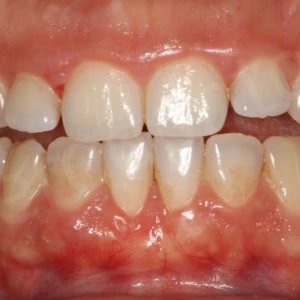

Hình 2 Ảnh chụp trong miệng trước điều trị

Bệnh nhân nữ trẻ, 24 tuổi được gia đình chuyển đến nha sĩ để tham khảo ý kiến (Hình 1) với lý do bị vẩu, các răng trước và rìa cắn các răng cửa dưới không đều (Hình 2-3). Bệnh nhân mong muốn giải quyết mà không phẫu thuật chỉnh hàm hoặc sử dụng minivis. Không có bệnh lý y khoa kèm theo nhưng bệnh nhân có tiền sử mất răng hàm nhỏ thứ hai ở hàm dưới bên trái và điều trị tuỷ không tốt ở cả hai răng hàm lớn thứ nhất bên trái. Khám lâm sàng ghi được tương quan răng hàm loại I bên phải, nhưng bên trái là loại III. Đường giữa răng hàm dưới lệch sang trái 2mm so với đường giữa mặt và hàm trên. Các răng cửa bên hàm trên bị lệch về phía khẩu cái cả hai bên.